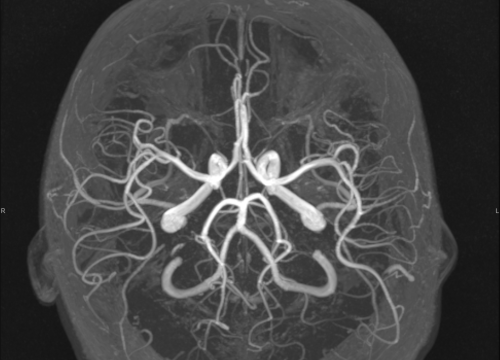

Ako su vam potrebni specijalistički pregledi mamografija, RTG, UZV, CT i MR, koji se inače koriste za dijagnostiku velikog broja zdravstvenih problema, možete ih obaviti već danas ili sutra.